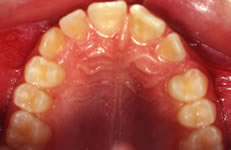

Terapia ortodontica - Prima (FIG 4)

La paziente S.A., di anni 12, presenta morso crociato posteriore monolaterale (fig. 1) dovuto a deviazione della mandibola verso destra in fase chiusura , pertanto le linee interincisive risultano non coincidenti (fig. 2). Si rileva inoltre l’assenza in arcata del canino superiore di sinistra ( incluso) e carenza di spazio per lo stesso (fig. 3 e 4).